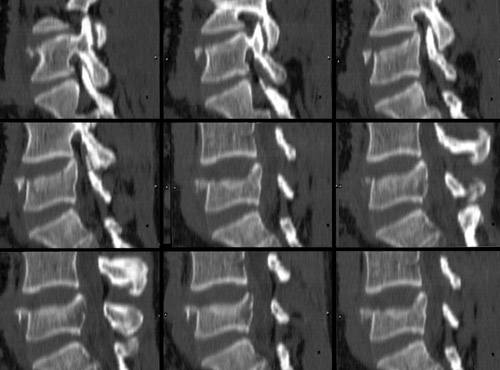

It is important that CT be performed to fully assess the spinal canal. The images below illustrate the appearance of a compression fracture as seen on CT.

Sagittal reconstruction of CT data

Note that in the images below, the posterior vertebral body is not intact.